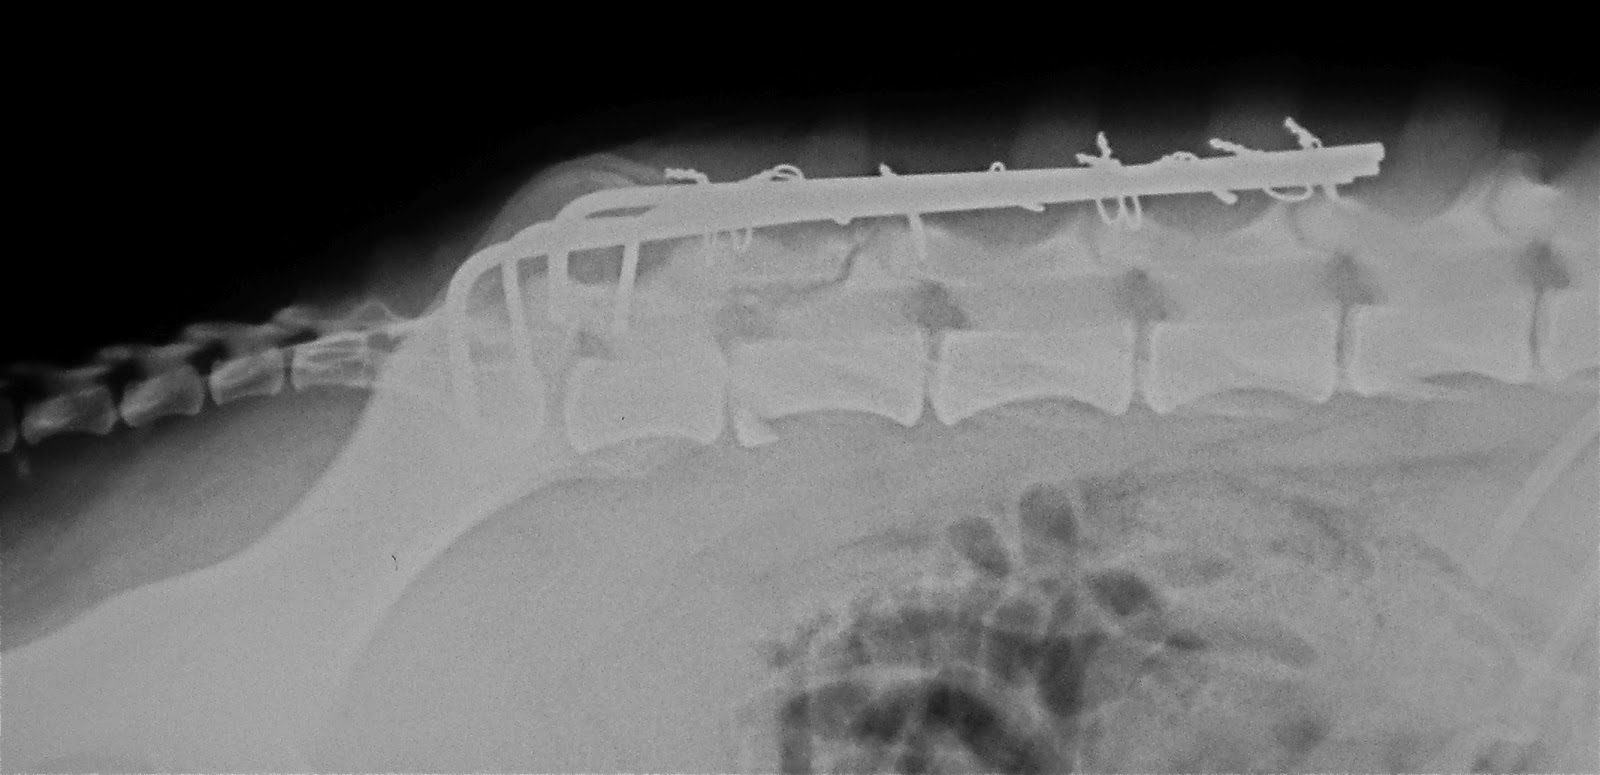

Στα ακτινογραφήματα, τα σπλάγχνα του θώρακος και της κοιλίας ελέγχθηκαν κατά φύση. Κατά τον έλεγχο της σπονδυλικής στήλης διαπιστώθηκαν εξάρθρημα μεταξύ του έκτου και του εβδόμου οσφυϊκού σπονδύλου και κατάγματα του σώματος, της ακανθώδους απόφυσης και του ραχιαίου πετάλου του έκτου οσφυϊκού σπονδύλου (Εικ. 1). Κατά τον έλεγχο της πυέλου διαπιστώθηκε προκοτύλιο-υπερκοτύλιο εξάρθρημα του δεξιού ισχίου.

Εικ.1: Ακτινογραφία της οσφυϊκής μοίρας της σπονδυλικής στήλης